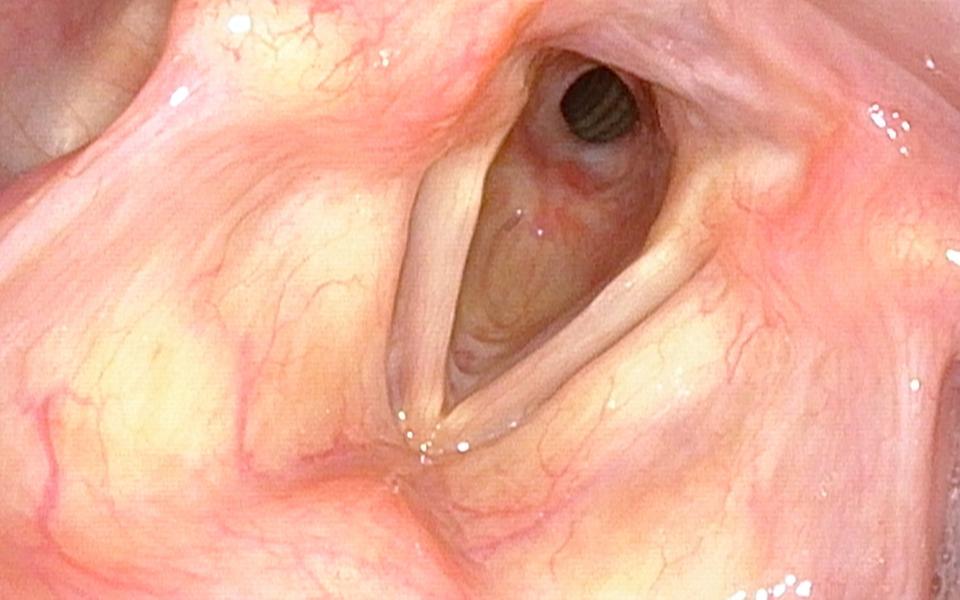

Supraglottitis